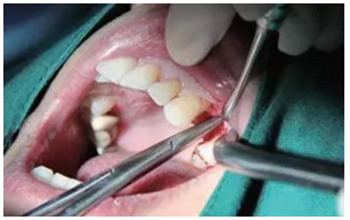

翻瓣與植入種植體

注意翻瓣不能太大,只需將窩洞頂端及周邊充分暴露即可。檢查種植窩洞頂端邊緣的骨壁情況,將窩洞頂端的高點去除,防止其干涉愈合基臺的就位。植入種植體植入時通過扭力扳手來確定最終的植入扭力,并判斷是否合適放置愈合基臺,也可以通過松動度測量儀測量ISQ值來判斷。

圖4 小翻瓣暴露窩洞頂端并去除高點